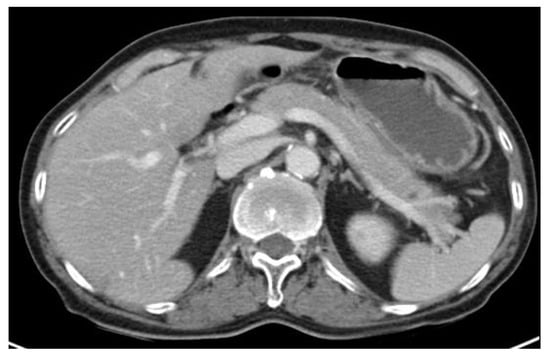

A 57-year-old Korean man was admitted for chemotherapy. The patient did not smoke or drink alcoholic beverages for religious reasons and exhibited no specific underlying diseases. Under ultrasonography performed due to sudden pain in his right testis, a 4cm-sized testicular mass was observed. Subsequently, he received right radial orchiectomy 26 days prior to hospitalization and was diagnosed with ENKTL nasal type through biopsy from surgical specimen. Paranasal sinus computed tomography (CT) was performed 14 days prior to hospitalization and no abnormal mass or mucosal edema was seen. In addition, CT in neck, chest, and abdomen were performed but no enlarged lymph nodes were observed throughout his entire body. There was no abnormal finding in positron emission tomography (PET) CT (Figure 1A). Bone marrow biopsy results showed normally matured myeloid/erythroid cell and normocellular marrow with reticulin grade 1 and 40% cellularity. At the time of hospitalization, blood test results showed elevated levels of lactate dehydrogenase (306 U/L) and Epstein-Barr virus polymerase chain reaction result (860.40 copies/uL), but all other measurements including complete blood count, liver function test, renal function test, electrolyte, amylase, and lipase levels were within normal range.

Figure 1.

Pancreas findings before chemotherapy. (A) There was no finding of presenting malignancy in pancreas on PET CT. (B) No abnormal findings suggestive of acute pancreatitis were observed in CT.